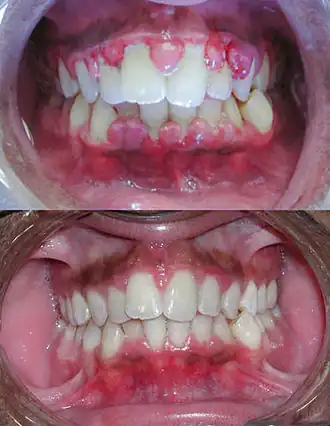

Gingivite hypertrophique ou hyperplasique

On observe une augmentation de volume importante (parfois on ne voit même plus les dents). La gencive est très fibreuse ; la texture et la teinte restent normales (car on ne voit pas la partie enflammée).

L'étiologie est la prolifération des fibroblastes. Elle est parfois d'origine idiopathique, mais le plus souvent elle est favorisée par certains médicaments : certains antiépileptiques, la ciclosporine, la nifédipine et certains bêta-bloquants).

- Gingivite hypertrophique, généralisée ou localisée (épulis). Dans ce cas, on pratique une gingivectomie, chirurgie simple, avec de bons résultats.